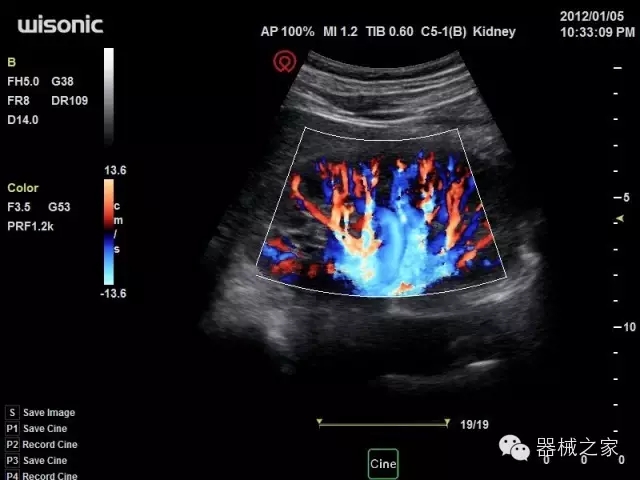

臨床圖片賞析

·亞陣元技術(shù):獨(dú)有的亞陣元技術(shù),對獨(dú)立晶片做二次切割,減少旁瓣偽像,增加臨床診斷的準(zhǔn)確性;

·μ-Scan微米成像技術(shù):開立獨(dú)有的μ-Scan技術(shù),還原出真實(shí)細(xì)膩、層次對比優(yōu)異的二維圖像;

·倒相諧波成像技術(shù):倒相諧波技術(shù)在去除基波信號的基礎(chǔ)上獲取兩倍二次諧波信號,提高組織圖像的對比分辨力;

·智能微血流成像技術(shù):智能微血流捕捉技術(shù)可以提取出隱藏在背景噪聲中的弱血流信號,大大提高低速血流的敏感性;